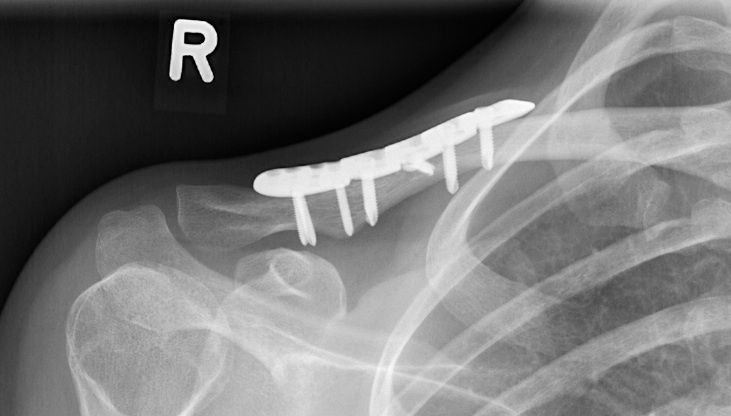

Neben der klassischen Frakturversorgung mittels Titanplatte und Schrauben stehen heute verschiedene Implantate zur Verfügung, die in den Markkanal eingebracht werden. Bei einfachen Frakturen im Schaftbereich kann der Bruch damit im Marknagel geschient werden. Komplexe, mehrfragmentäre Bruchformen und verschobene Brüche im äußeren Drittel werden am besten mit einer winkelstabilen Platte versorgt.